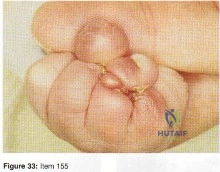

- Clinodactyly

- Camptodactyly

- Symbrachtyly

- Kirner’s deformity

- Digiti minimi adductus